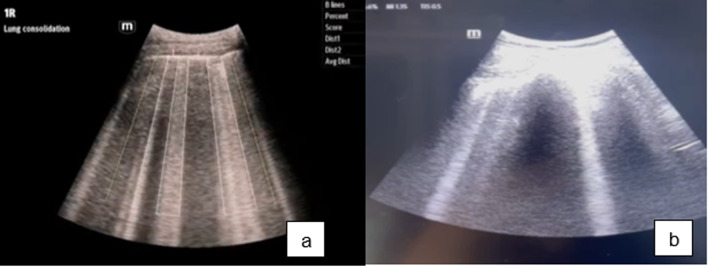

Purpose: B-lines in lung ultrasound have been a critical clue for detecting pulmonary edema. However, distinguishing B-lines from other artifacts is a challenge, especially for novice point of care ultrasound (POCUS) practitioners. This study aimed to determine the efficacy of automatic detection of B-lines using artificial intelligence (Auto B-lines) for detecting pulmonary edema.

Results: Sixty-six patients with a final diagnosis of pulmonary edema were enrolled, with 54.68% having positive B-lines in lung ultrasound. Auto B-lines had 95.6% sensitivity (95% confidence interval [CI]: 0.92-0.98) and 77.2% specificity (95% CI: 0.74-0.80). Physicians demonstrated 82.7% sensitivity (95% CI: 0.79-0.97) and 63.09% sensitivity (95% CI: 0.58-0.69).

Conclusion: The auto B-lines were highly sensitive in diagnosing pulmonary edema in novice POCUS practitioners. The clinical integration of physicians and artificial intelligence enhances diagnostic capabilities.